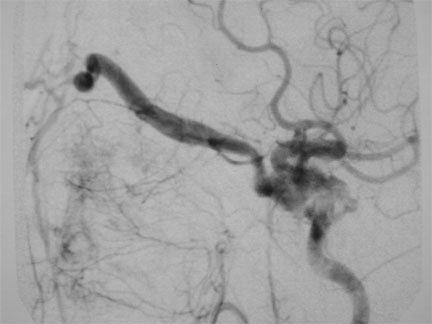

CASO 2 : Embolización de fístula carótidocavernosa con antecedente de traumatismo craneal

Antes del tratamiento por embolización de fístula carótidocavernosa

Instantes d espués de la embolización de la fístula carótido-cavernosa